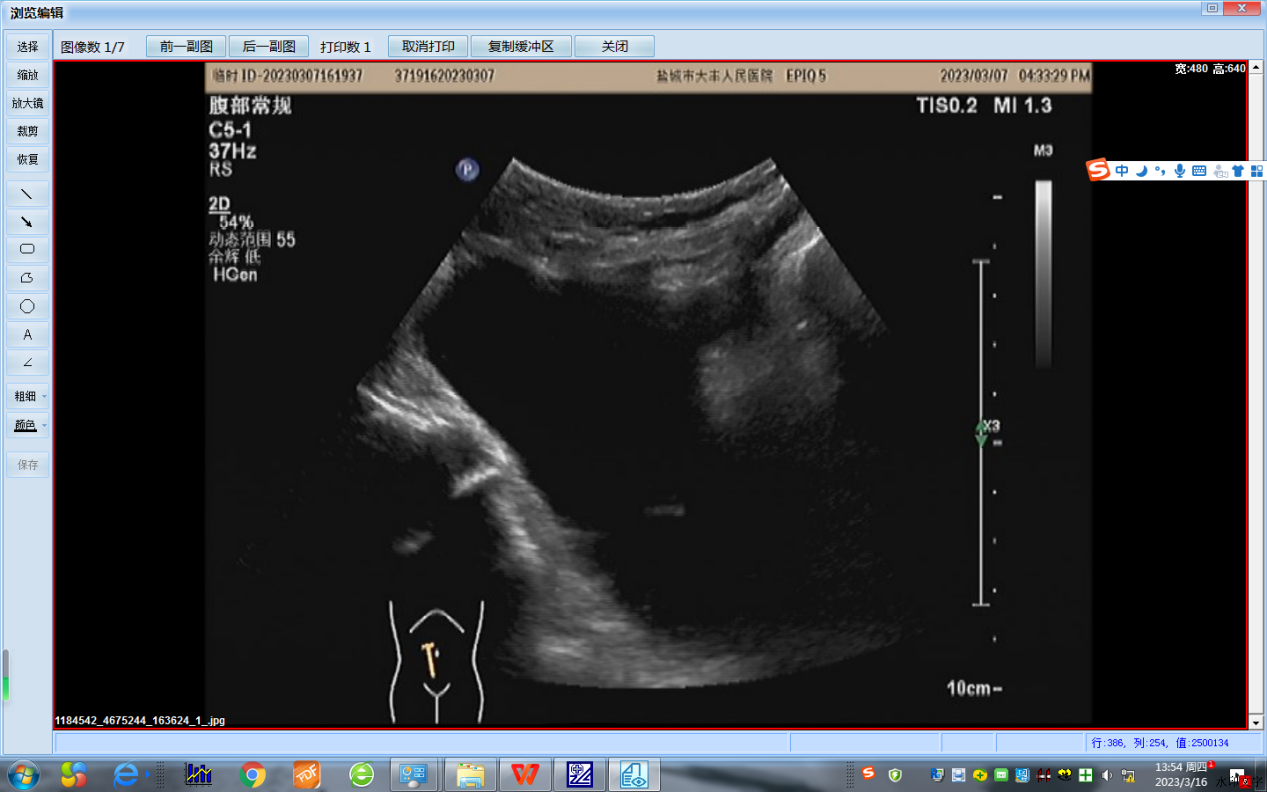

患者为一86岁老年女性,因“下腹部隐痛3天”至我院检查,彩超提示:盆腔内巨大囊性肿物,大小约112×74㎜。由于患者囊性包块较大且出现盆腔压迫症状,结合CA125、199等肿瘤指标及CT影像学检查,基本排除恶性可能。妇产科杨秀萍主任组织病案讨论,因患者年龄较大,驼背明显,心肺功能不全,行动不便,外科创伤手术耐受性较差,故考虑行超声引导下卵巢囊肿穿刺硬化治疗。超声科姜建军主任团队对患者进行仔细检查综合评估后,确定可以借助微创介入治疗解决。征得患者及家属的同意后,为了保障手术安全,姜主任团队对术中可能出现的突发情况进行了详细充分的讨论,并提出多种方案供术中参考,同时加大对患者的心理疏导,消除她的术前恐惧情绪,使老人以最佳状态接受手术治疗。术中,在超声引导下,穿刺针准确的进入囊肿的中心,随着囊液不断被抽出,囊肿变小,不断的调整针尖位置,最终将囊内的液体全部抽出,抽出约260ml淡黄色液体,并注入硬化剂,顺利的完成手术。

穿刺前